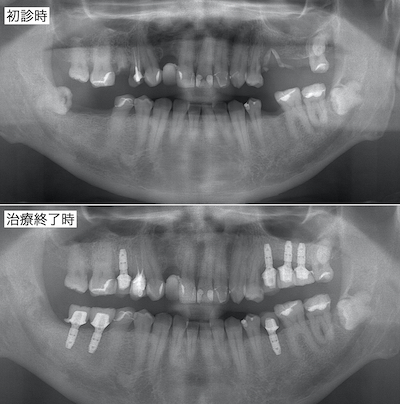

初診時と術後のレントゲンです。